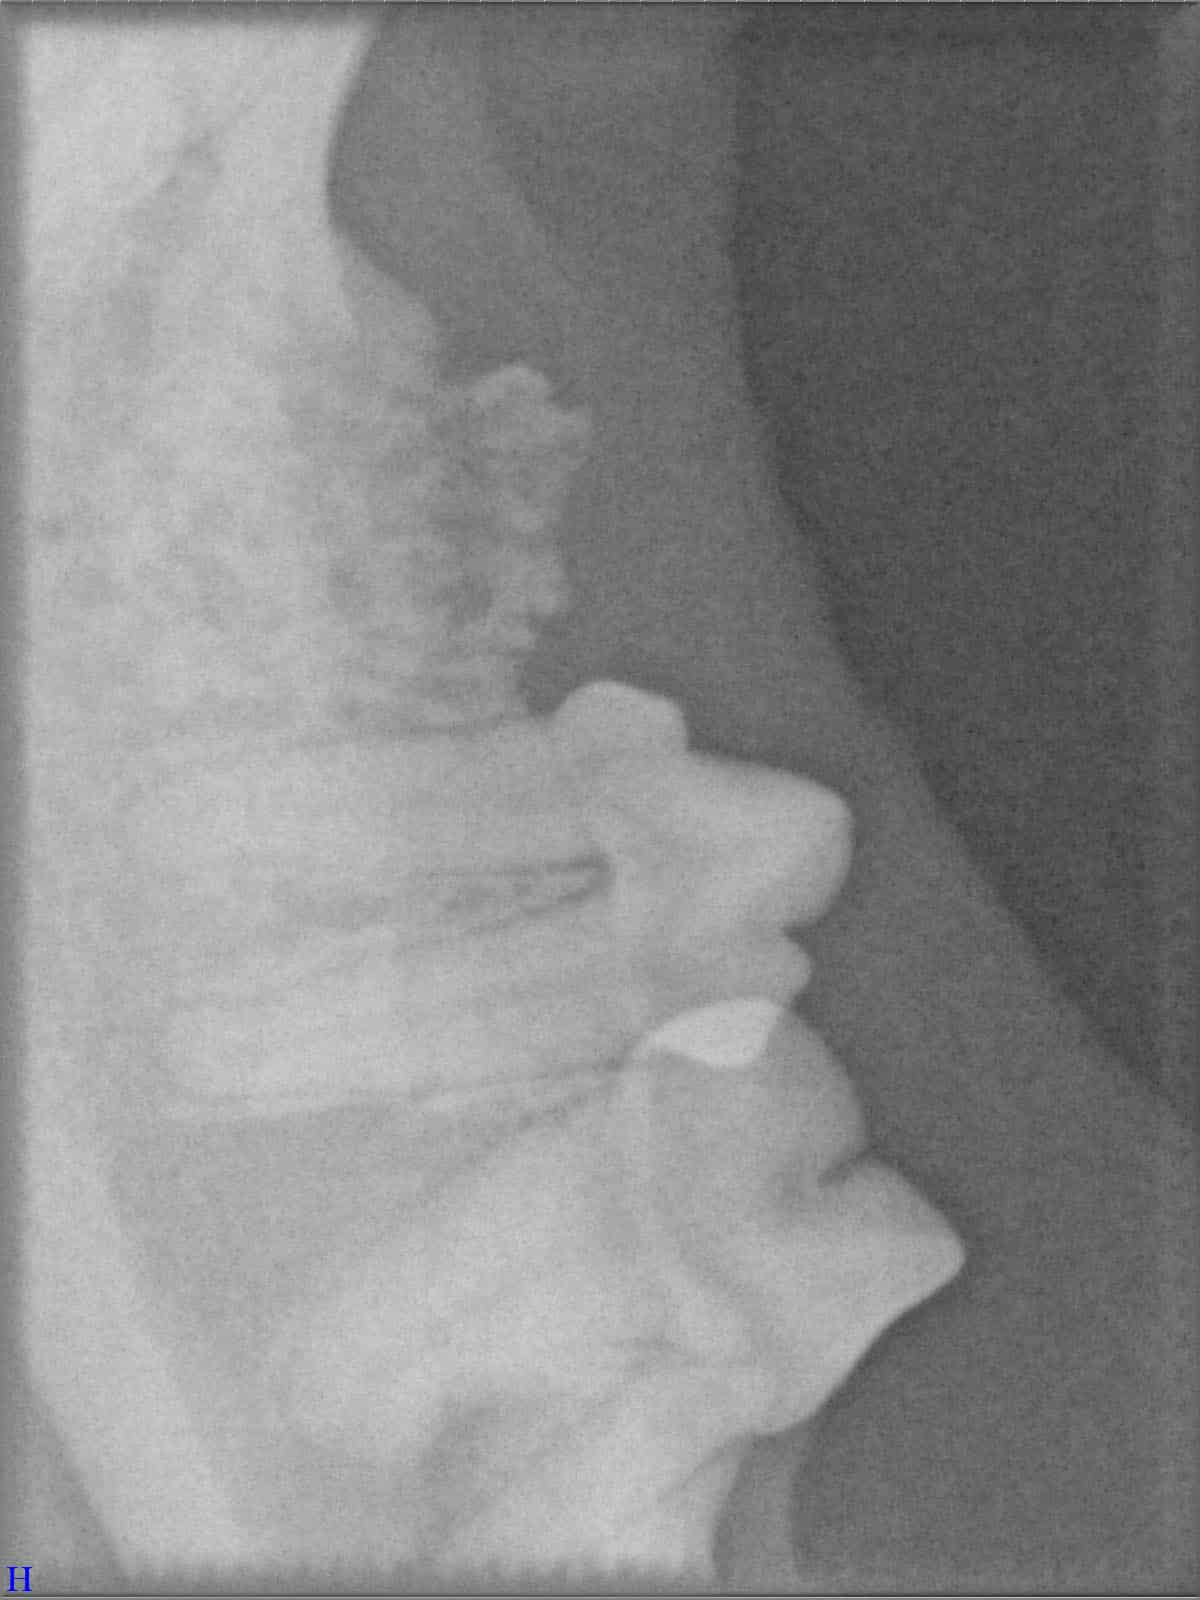

Ein entscheidender Baustein der FORL-Diagnostik ist das dentale Röntgen. Viele Läsionen sind von außen nicht sichtbar und lassen sich ausschließlich mithilfe moderner Röntgentechnik erkennen. In der Hamburger Praxis kommt digitales Dentalröntgen zum Einsatz, das detailreiche Aufnahmen bei geringer Strahlenbelastung ermöglicht. So kann FORL bereits in frühen Stadien diagnostiziert werden.

Das sehen Sie von außen – so sieht es auf den Röntgenbildern aus.

FORL Katze Röntgenbild

Röntgenbilder